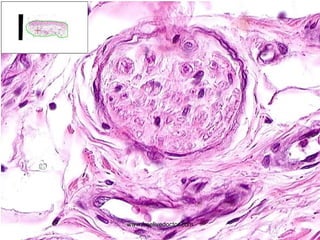

• #47 Schwannoma

Antoni  A : “Palisaded”  Antoni  B : NON-Palisaded www.freelivedoctor.com